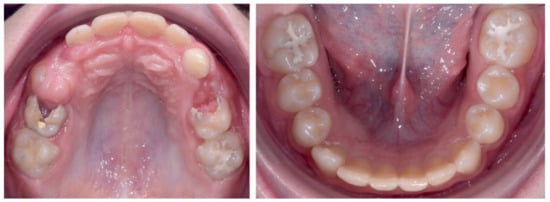

2.2.1. Initial Examination